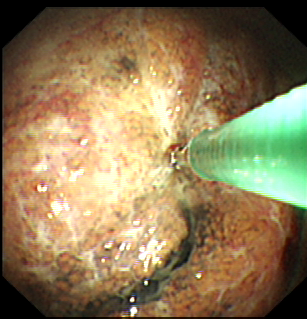

近年来,贵州航天医院各科室紧跟医学前沿,不断强技术、补短板,大力开展新技术、新项目,完成了许多高精尖、高难度、本地区“首例”的技术,填补了医院医疗技术空白,满足了群众日益增长的医疗需求。 贵州航天医院呼吸与危重症医学科是贵州省内呼吸疾病治疗规模最大,诊疗项目最全的呼吸疾病品牌科室,呼吸介入技术达到了全国先进水平,在贵州省内处于领先的地位。 本期,我们将为大家带来呼吸与危重症医学科特色技术——内科胸腔镜技术诊断和治疗胸腔疾病。 案例分享 患者苟某某,因劳累、气促,不明原因胸腔积液在某县一医院采取反复抽水等治疗手段效果不佳,当地医院考虑到患者年龄大(77岁),基础疾病较多,病情复杂,结合当地诊疗水平能力情况,建议转到上一级医院诊治,通过我院与该院建立的呼吸专科联盟绿色通道转入了我院。 患者入院后,呼吸与危重症医学科第一时间复查胸部CT,提示:右肺中叶、左肺感染,纤维化灶,左侧中量胸腔积液,右后侧胸膜轻度增厚,心包少量积液;并完善心电图、血常规、凝血功能、生化指标等术前检查。经科室专家团队集体讨论,得出患者左侧胸腔积液可能原因:结核?恶性?其他?冠心病、心功能不全、高血压病3级(高危组)、陈旧性肺结核复发?肺部感染;为进一步明确诊断,在充分评估、做好术前准备及应急预案、与患者及家属沟通的情况下,决定为患者进行内科胸腔镜检查术。 科室在患者入院第3天便实施了内科胸腔镜检查术,经检查取活检,病理不排除胸膜间皮瘤,送遵义医科大学附属医院病理会诊后诊断:胸膜间皮瘤。明确诊断后,科室专家团队为患者制定了个体化的治疗方案,患者病情很快得到有效控制,最终满意出院。半年后,医院通过电话回访,患者病情稳定,生活质量明显改善。 什么是内科胸腔镜 内科胸腔镜(medical thoracoscopy,MT)是一项微创诊断和治疗胸腔疾病的重要技术。主要应用于无创方法不能确诊的胸腔积液和胸膜疾病,通过局部麻醉后在胸壁做一个小切口,插入胸腔镜,直接观察胸膜、肺表面、纵隔等部位的病变情况,可进行活检、粘连松解及胸膜固定等操作。具有创伤小、恢复快、诊断准确性高等优点。 内科胸腔镜原理 内科胸腔镜是一项利用现代光学技术和成像技术的侵入性操作技术,应用电子支气管镜、硬质或软硬结合(半硬)的胸腔镜的一种电子内窥镜,末端装有连接着显示屏的微型摄像头。通过胸壁1-2cm左右的小切口,将内科胸腔镜及专用器械(戳卡套管)通过小切口进入胸腔,微型摄像头将胸腔内的情况投射到显示屏幕上,医生可以通过镜头全面、直观地观察患者胸腔内情况,了解胸膜病变确切位置和形态改变,还可对胸膜上的病变进行活检及治疗的操作技术,安全、微创、几乎无痛地“揭秘”不明原因的胸腔积液。 内科胸腔镜技术优势 (一)安全性高:仅需局部浸润麻醉,并发症发生率相对较低,对患者的身体条件要求较低。 (二)操作简便:操作时间短,痛苦少,患者耐受好。 (三)微创性:切口小,对患者身体损伤小,术后疼痛轻,恢复快。 (四)高分辨率成像:清晰显示胸腔内细微病变,提高诊断准确性。 (五)可直视操作:直接观察病变,进行精准活检和治疗。 (六)适用范围广:可用于不明原因胸腔积液、胸膜疾病、肺部疾病等的诊断和治疗。 (七)费用低:与外科胸腔镜比较费用低廉。 内科胸腔镜技术是贵州航天医院呼吸专科和呼吸介入诊疗优势的一部分,在2016年率先开展了内科胸腔镜技术,年手术量约100余例,已建立了快速、精准、规范、有效的一体化诊疗服务体系。目前呼吸与危重症医学科内科胸腔镜技术广泛应用于不明原因胸腔积液、气胸、脓胸的诊断和肺癌、弥漫性恶性胸膜间皮瘤等的分期,恶性或复发性胸腔积液、早期脓胸、自发性顽固性气胸的治疗。 镜下常见表现:单发或多发结节、灰白色弥漫性粟粒样结节、胸膜充血、水肿、胸膜增厚及纤维分隔或粘连带形成。 诊断方面: 胸腔积液的病因诊断。内科胸腔镜对恶性胸腔积液的诊断率可高达90%以上,胸腔镜对结核性病变诊断率极高,几乎达到96%以上。 腺 癌 恶性淋巴瘤 软骨肉瘤胸膜转移 滑膜肉瘤胸膜转移 结核性胸膜炎 治疗方面: 脓胸 肺大泡 贵州航天医院 呼吸与危重症医学科学科带头人 廖江荣 国务院政府特殊津贴专家 二级教授 主任医师 贵州航天医院副院长 国家级学术任职: 第二届中国医药教育协会介入微创专业委员会呼吸分会副主任委员 中国抗癌协会肿瘤微创治疗专业委员会常务委员 中国防痨协会结核病转化医学专业分会常务委员 第一届中国人体健康科技促进会呼吸介入专委会常务委员 中国医疗保健国际交流促进会结核病学分会第三届委员会常务委员 中国抗癌协会肿瘤微创治疗专业委员会粒子治疗学组第四届委员会委员 中华医学会结核临床专业委员会内镜介入委员 中华医学会放射学分会第十五届委员会介入学组呼吸系统介入专业委员会委员 北京健康促进会中青年专家委员会胸部疾病精准活检分委会副主任委员 中国医师协会介入医师分会第二届委员会肿瘤消融专业委员会委员 中国结核病防治综合质量控制专家指导委员会委员 亚洲冷冻治疗学会常务委员 世界内镜医师协会呼吸内镜协会常务理事 内镜临床诊疗质量评价专家委员会委员 “西部呼吸介入联盟”副理事长 专业擅长: 贵州航天医院 呼吸与危重症医学科简介 贵州航天医院呼吸与危重症医学科以呼吸危重症和介入呼吸病学为强力推手,以肺部感染性疾病及肺癌、肺小结节的早期精准诊疗、慢性呼吸疾病康复治疗为特色,以人才团队建设为核心的科室发展模式,现已成为省内呼吸疾病治疗规模最大,诊疗项目最全的呼吸疾病品牌科室。是贵州省医学重点学科、临床医学重点专科建设单位,遵义市首批呼吸重点学科、重点专科建设单位。是国家卫健委能力建设和继续教育肿瘤微创介入建设中心、贵州省县级医院微创介入培训中心、遵义市呼吸疾病临床医学中心。是国家呼吸医疗质量控制与管理哨点医院、遵义市呼吸内科专业医疗质量控制中心。是中国医药教育协会介入微创呼吸分会呼吸介入技术培训中心单位;国家卫健委海医会呼吸分会ROSE专委会“诊断性介入肺脏病学快速现场评价”培训基地;中国肺癌防治联盟“贵州航天医院肺结节诊治”分中心,中国人体健康科技促进会呼吸介入技术培训基地,贵州省中西医结合会呼吸学分会呼吸介入专委会主委单位。 基本情况 平均每年开展气管镜诊疗约4000例,经皮肺穿刺介入诊疗近千例,开展的项目包括经支气管镜(软、硬)下冷冻、氩气刀、高频电刀、球囊扩张、支架置入、超声内镜诊疗等气道介入诊疗技术,经皮肺穿刺活检及肿瘤消融术(微波、冷冻)、ROSE技术、内科胸腔镜诊疗及经血管介入诊疗技术,且多项呼吸介入诊疗技术在省内处于领先水平。 诊疗范围 航天医院呼吸专科擅长:致力于呼吸系统感染性、疑难性疾病的介入快速精准诊疗;肺癌与肺小结节早期精准诊疗水平项目提升。擅长于呼吸系统(肺)疑难病的诊断及危重病的救治,尤其在肺癌、肺小结节的早期诊断;肺癌综合靶向治疗;肺结核综合诊疗;肺部疾病的介入诊疗在省内处于前沿水平。 咨询热线 (一)呼吸与危重症医学科一病区 医生办公室:27677317 护士站:28614217 (二)呼吸与危重症医学科二病区 医生办公室:28691274 护士站:28690442 (三)呼吸与危重症医学科三病区 医生办公室:28692417 护士站:28690461 (四)呼吸与危重症医学科四病区 医生办公室:28616402、27677582 护士站:28614987、27677862